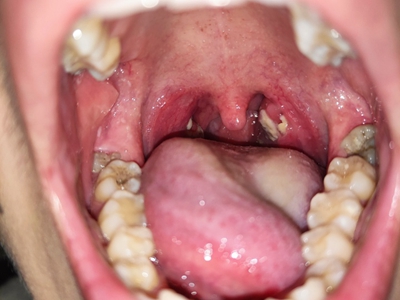

化脓性扁桃体炎单侧扁桃体变大化脓图

化脓性扁桃体炎咽部单侧扁桃体肿大突出,颜色呈鲜红色,形状不规则,黏膜表面凹凸不平,附有黄白色物质,伴有明显疼痛等自觉症状。